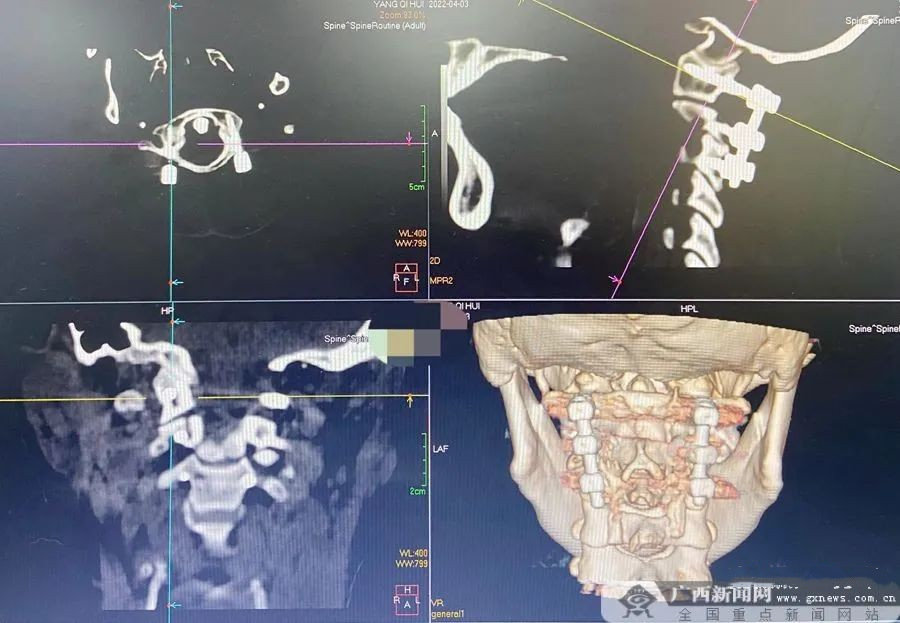

该患者因颈部外伤被诊断为枢椎骨折脱位(医学上又称Hangman骨折),需要进行手术治疗,而寰枢椎解剖结构特殊、椎弓根细小、本身有骨折脱位,个体变异性大、毗邻颈脊髓及椎动脉等重要组织,若置钉位置不当,易造成上述组织损伤,同时还可能影响到内固定系统的稳定性。

△匹配上颈椎解剖形态的3D打印导板。广西新闻网通讯员 李亮 供图

该院脊柱外科团队经讨论后,决定运用3D打印技术,为患者定制导板辅助手术。3D打印导板基于三维重建模型可规划椎弓根螺钉的最佳进钉点、进钉角度及螺钉的长度。同时根据椎体棘突、椎板、关节突关节等解剖形态反向建立与之相匹配的导板,术中将导板贴附于相应椎体后部骨性结构,沿定位孔便可准确地对椎弓根置钉。此方法大大提高了置钉准确性,减少手术时间及透视次数,降低了手术难度,使复杂的手术简单化。该患者的手术仅耗时1个小时便顺利完成。

△术后复查上颈椎CT显示螺钉位置良好。广西新闻网通讯员 李亮 供图